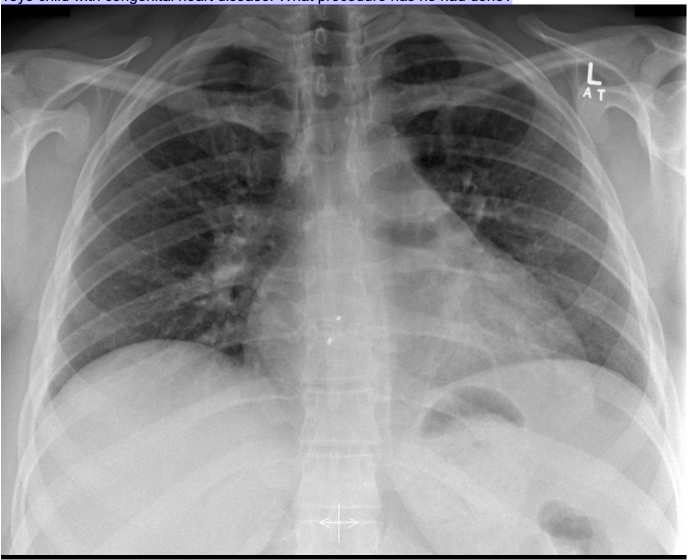

20.1 What is the abnormality in this CXR?

a. Pneumonectomy

b. Pleural effusion

c. Pneumonia

d. Unilateral pulmonary oedema

Complete white-out of left lung with air bronchogram sign consistent with total consolidation. Patchy areas of ground glass opacities in right lung. There is silhouetting of the left heart border and left hemi-diaphragm. There is no rib crowding to suggest atelectasis.

Complete white-out of the hemithorax with air bronchograms and trachea in a central position is consistent with consolidation secondary to pneumonia. The patient is on linezolid, micafungin, and piperacillin-tazobactam pending culture and susceptibility studies.

Differential diagnosis of hemithorax white-out with a midline trachea include:

- consolidation

- pulmonary edema/ARDS

- pleural mass

- chest wall mass